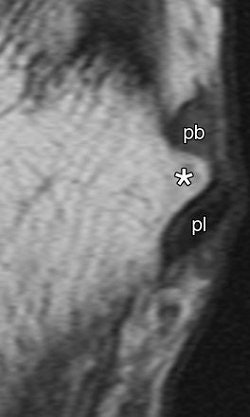

| Enlarged peroneal tubercle. T1-weighted MR images in (above) transverse oblique (45° between coronal and transverse planes, 572/14) and (below) coronal (572/14) planes show enlarged peroneal tubercle (*) in 60-year-old male asymptomatic volunteer. pb = peroneus brevis tendon, pl = peroneus longus tendon. |

"The median size of the peroneal tubercles was 2.6 mm on transverse oblique T1-weighted images and 2.9 mm on transverse T2-weighted images," the authors wrote. "The mean angle between the plantar fascia and the longitudinal axis of the tibia was 98˚" (Radiology, February 2007, Vol. 242:2, pp. 509-517).

- The term "enlarged peroneal tubercule" and "enlarged retrotrochlear eminence" should only apply to structures of more than 5 mm.